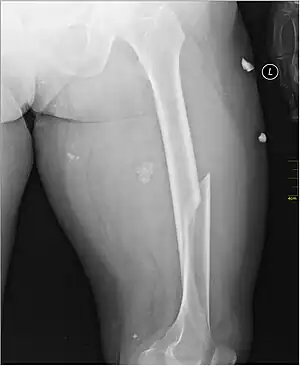

| X-ray image of a femoral shaft fracture | |

A femoral fracture is a bone fracture that involves the femur. They are typically sustained in high-impact trauma, such as car crashes, due to the large amount of force needed to break the bone. Fractures of the diaphysis, or middle of the femur, are managed differently from those at the head, neck, and trochanter; those are conventionally called hip fractures (because they involve the hip joint region). Thus, mentions of femoral fracture in medicine usually refer implicitly to femoral fractures at the shaft or distally.